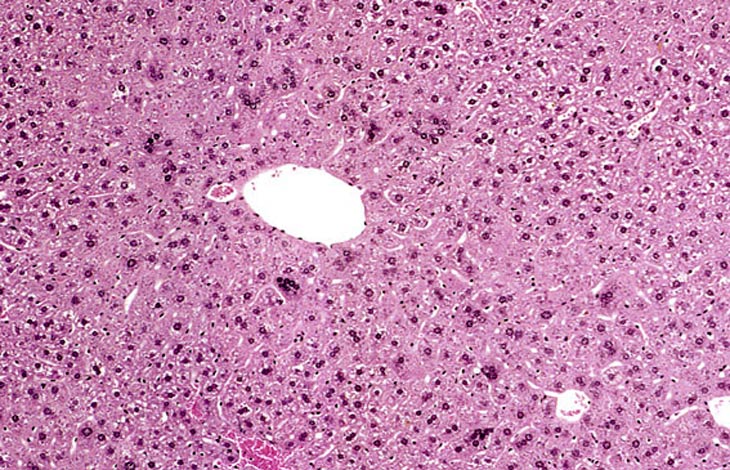

Adult mouse liver with scattered multinucleated hepatocytes

A mouse treated chronically with chlordane, showing enlarged hepatocytes with multiple nuclei.

Multinucleated hepatocytes in a B6C3F1 male mouse.